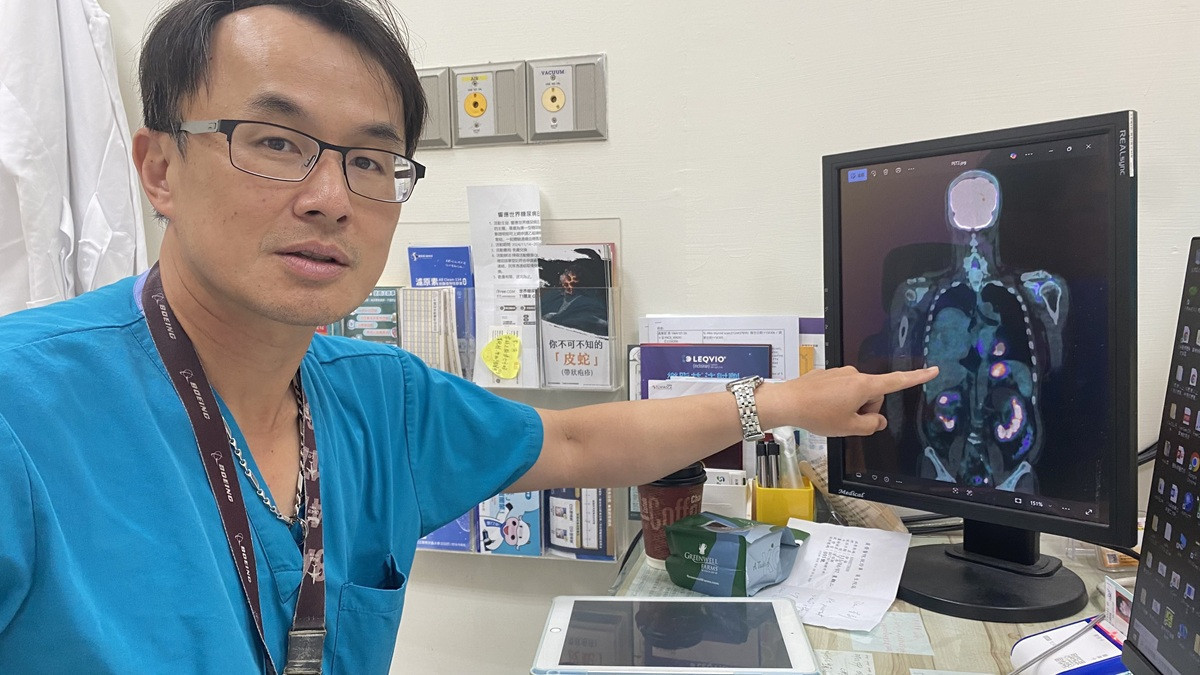

因此會診胸腔內科醫師涂川洲副院長,醫療團隊評估後高度懷疑為「腫瘤相關低血糖」,可能與腫瘤分泌類胰島素生長因子(IGF-2)有關,屬於罕見的「非胰島素瘤性低血糖症(NICTH)」。此類情況多見於大型腫瘤,尤其是間質性或纖維性腫瘤。

跨科會診後,轉由在員榮駐診的胸腔外科醫師、秀傳醫院李佳穎副院長手術。因腫瘤超過20公分,且侵犯肺葉及心包膜,因此特用胸腔鏡輔助迷你開胸手術(VATS-assisted minithoracotomy )以完整切除。